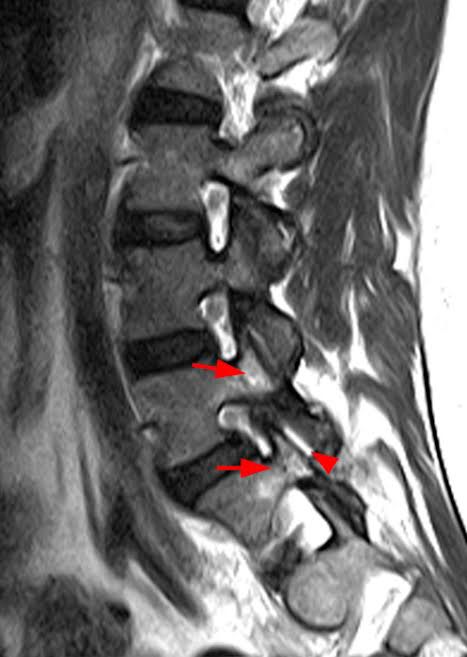

3. وبعد ذلك يتم طلب الأشعات السينية (العادية) و الرنين المغناطيسي، وأحياناً الأشعة المقطعية، التي عادةً ما تُبَيِّن بوضوح وجود خشونة واحتكاك وتآكل أو زوائد عظمية في المفصل المريض.

وعلى الرغم من أن المرض قد يصيب أكثر من مفصل إلا أنه عادةً ما يتركز في مفصل أو مفصلين بشكل كبير ويكونان مسؤولين عن الأعراض التي يشعر بها المريض